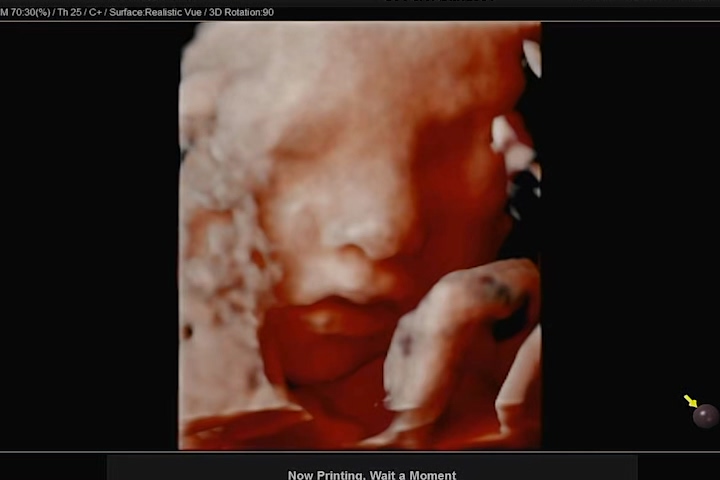

우리 까꿍에 엄마 뱃속의 태반에 머리를 기대고 한쪽 손을 올리고 있어 깔끔하게 얼굴을 보지 못했지만, 나름 만족하게 얼굴을 볼 수 있었다. 사실 이번 초음파 사진 정도까지도 기대하지 않고, 코와 입술 살짝만 나왔으면 좋겠다 했건만 그 이상의 모습도 보여줬다.

잠을 자고 있는지 평소에 비해 움직임이 없던 까꿍이. 보통 3D 초음파는 눈을 감고 있기 때문에 눈 부분은 디테일하게 나오지 않는다고 하셨다. 그래도 영상 중간중간과 초음파 사진에는 눈 윤곽도 나와있어서 얼굴의 형태를 느낄 수 있었다.

입술은 아내를 닮은 것 같고, 코는 나를 닮은 것 같고..ㅎㅎ 서로가 서로를 닮았다며 말했다. 우리 둘을 닮은 아이 아직은 신기하고 귀엽기만 했다. 3D 초음파 검사비용은 병원마다 상이하지만 우리가 다니는 산부인과에서는 6만원이었다.